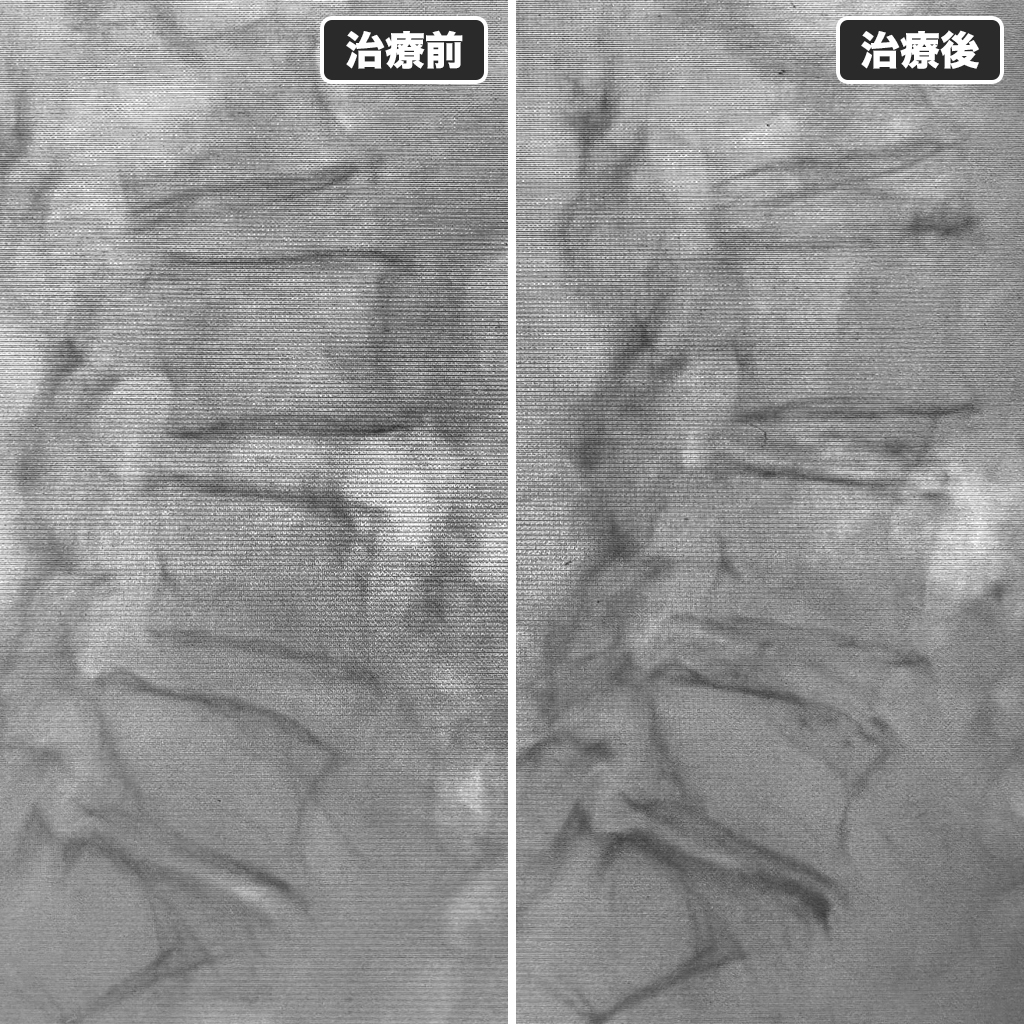

Annulargram検査

Annulargram検査になります。椎間板繊維輪の損傷部分が確認されます。空気圧検査でも椎間板内圧低下が確認されましたので、減圧治療(PLDD・オゾン治療・ディスコゲル=セルゲル法)は適応外と判断し、DRT法(椎間板再生治療)を選択いたしました。